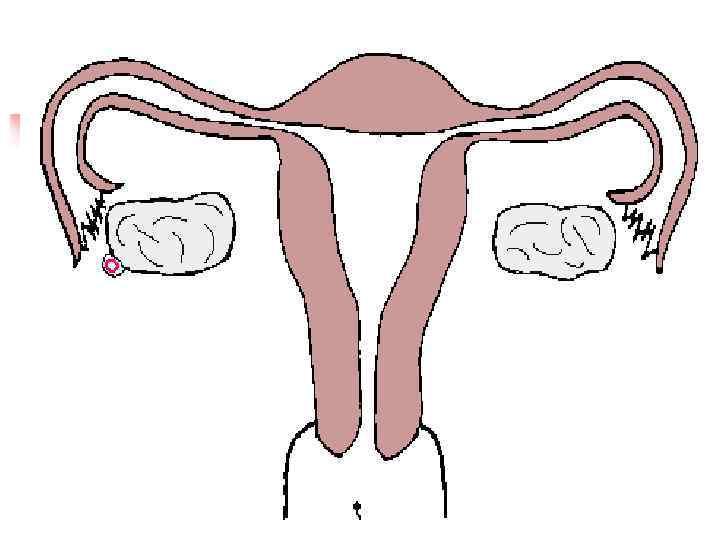

Эктопическая беременность n Трубная беременность – 95 99% n Яичниковая беременность n Брюшная беременность n Шеечная беременность

Причины эктопической беременности Воспалительные заболевания придатков матки n Половой инфантилизм n Пороки развития матки n Спайки в брюшной полости n Применение гормональной и внутриматочной контрацепции n

Морфологические признаки эктопической беременности n Анатомически: труба расширена, с кровоизлияниями, плодное яйцо n Гистологически: ворсины хориона, фибриноид, децидуальная реакция